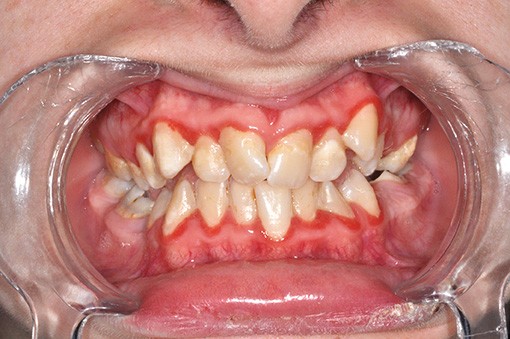

Ainsi, l’adolescent inquiète. Ses caractéristiques représentent autant de freins à l’instauration d’une alimentation et d’une hygiène bucco-dentaire propices à un état bucco-dentaire satisfaisant et sont à l’origine d’un désintérêt pour les soins ou pour un éventuel traitement orthodontique (fig. 1).

Après l’intervention de Caroline Delfosse, MCU-PH en odontologie pédiatrique à Lille, sur les aspects particuliers de la relation de soin avec l’adolescent, Jean-Pierre Attal, MCU-PH à Paris Descartes, abordera la question très actuelle de l’érosion-infiltration. Cette technique, initialement développée pour stopper le processus carieux dans les secteurs postérieurs, trouve des indications dans la prise en charge des défauts esthétiques antérieurs (white spot, fluorose, dyschromies post-traumatiques). Il présentera également de nouvelles propositions thérapeutiques permettant de traiter les cas de MIH antérieurs qui sont souvent à l’origine de demandes esthétiques fortes (fig. 2).